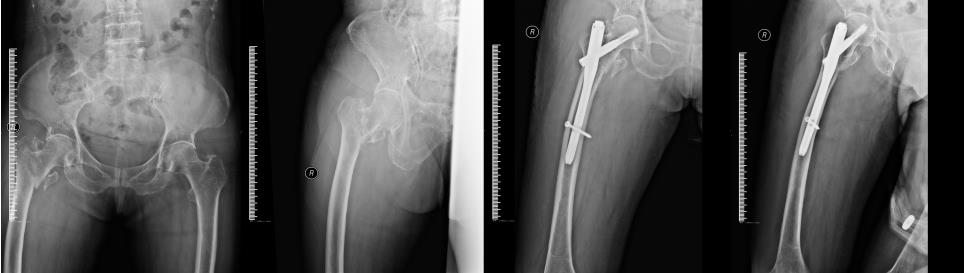

右股骨粗隆间骨折,行微创闭合复位PFNA髓内钉内固定治疗。